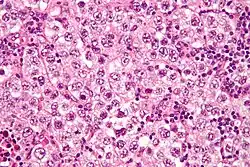

| Micrograph of a germinoma, H&E stain | |

The tumor is uniform in appearance, consisting of large, round cells with vesicular nuclei and clear or finely granular cytoplasm that is eosinophilic. On gross examination, the external surface is smooth and bosselated (knobby), and the interior is soft, fleshy, and either cream-coloured, gray, pink, or tan. Microscopic examination typically reveals uniform cells that resemble primordial germ cells. Typically, the stroma contains lymphocytes, and about 20% of patients have sarcoid-like granulomas.